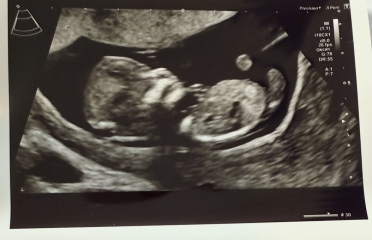

Rainbowbaby25 · 01/06/2025 11:54

Mixed opinions on other forums.

Girl because of bladder position and forked nub, also under 30 degrees and only slightly upward.

Others saying boy because of skull and the nub pointing more up then parrell but not to spine.

12+4 scan